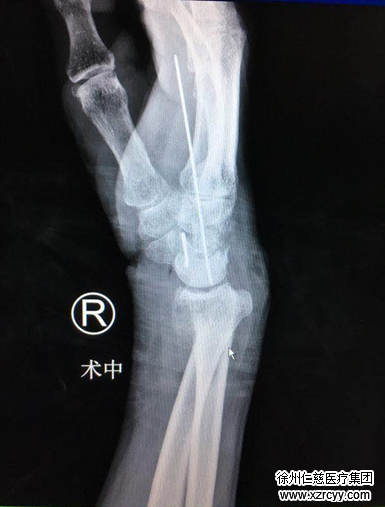

前天,在扛货时的老周一个趔趄摔倒在地,老周右手掌猛地一撑地,顿时觉得手腕一阵酸痛,老周以为过几天就好了,并未在意,谁知三天过去了,手腕肿胀得更加厉害,而且手指发麻,在当地医院开了药服用,可还是缓解不了手腕的疼痛与肿胀,后来拍完片子才知道,老周是月骨脱位,医生建议立即进行复位治疗,老周却认为没有必要,回家休养几天肯定能好。但事与愿违,耽误了近一个月,老周手腕疼痛加剧,难以忍受,遂被子女带到betway在线登陆进行进一步诊治。

betway在线登陆的齐伟亚主任介绍说,月骨骨形状特殊,掌侧宽背侧窄。临床漏诊率很高,脱位后完全移向掌侧,当月骨脱位时,腕部活动受限,手指屈曲困难,腕关节不能背伸,并可触到脱出的月骨,早期可采取手法复位,避免手术切开,由于老周执意不做复位治疗耽误了治疗进程,本应可以通过手法复位解决的脱位现在必须通过手术才能进行治疗。